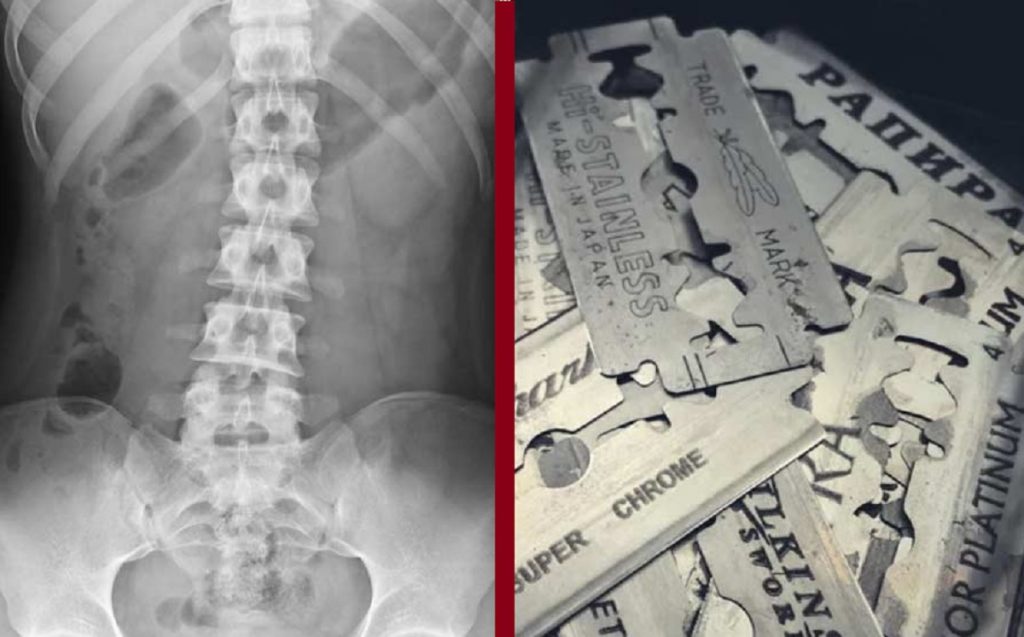

চিকিৎসকরা জানিয়েছেন, কাউকে না জানিয়েই চুপিসারে দিনের পর দিন ব্লেড খেতেন ওই যুবক। তারপর হঠাৎ গত সোমবার রক্তবমি শুরু হয় তার। তারপর হাসপাতালে নেয়া হলে এক্স-রে, আলট্রাসাউন্ড এবং এন্ডোস্কোপি শেষে দেখা যায়, তার পেটের মধ্যে অসংখ্য ব্লেডের টুকরা রয়েছে। তারপরই সময় নষ্ট না করে অস্ত্রোপচার করার সিদ্ধান্ত নেন ডাক্তাররা।

দীর্ঘ ৩ ঘণ্টার অস্ত্রোপচার শেষে চিকিৎসকরা ওই যুবকের পেট থেকে ব্লেডের ৫৬টি টুকরা বের করেছেন। তারা জানিয়েছেন, ওই যুবক গোটা একটি ব্লেডকে ভেঙে দুটি টুকরা করে গিলে ফেলেন। শরীরের মধ্যে দিয়ে যাওয়ার সময়ে অঙ্গ-প্রত্যঙ্গের ক্ষতি হওয়ায় তার রক্তবমি শুরু হয়। তবে অস্ত্রোপচারের পর যুবকের শারীরিক অবস্থা স্থিতিশীল আছে। কিন্তু এতো খাবার থাকতে হঠাৎ কেন ব্লেড খেতে হলো তাকে? এমন প্রশ্নের কোনো জবাব দেননি ওই যুবক।